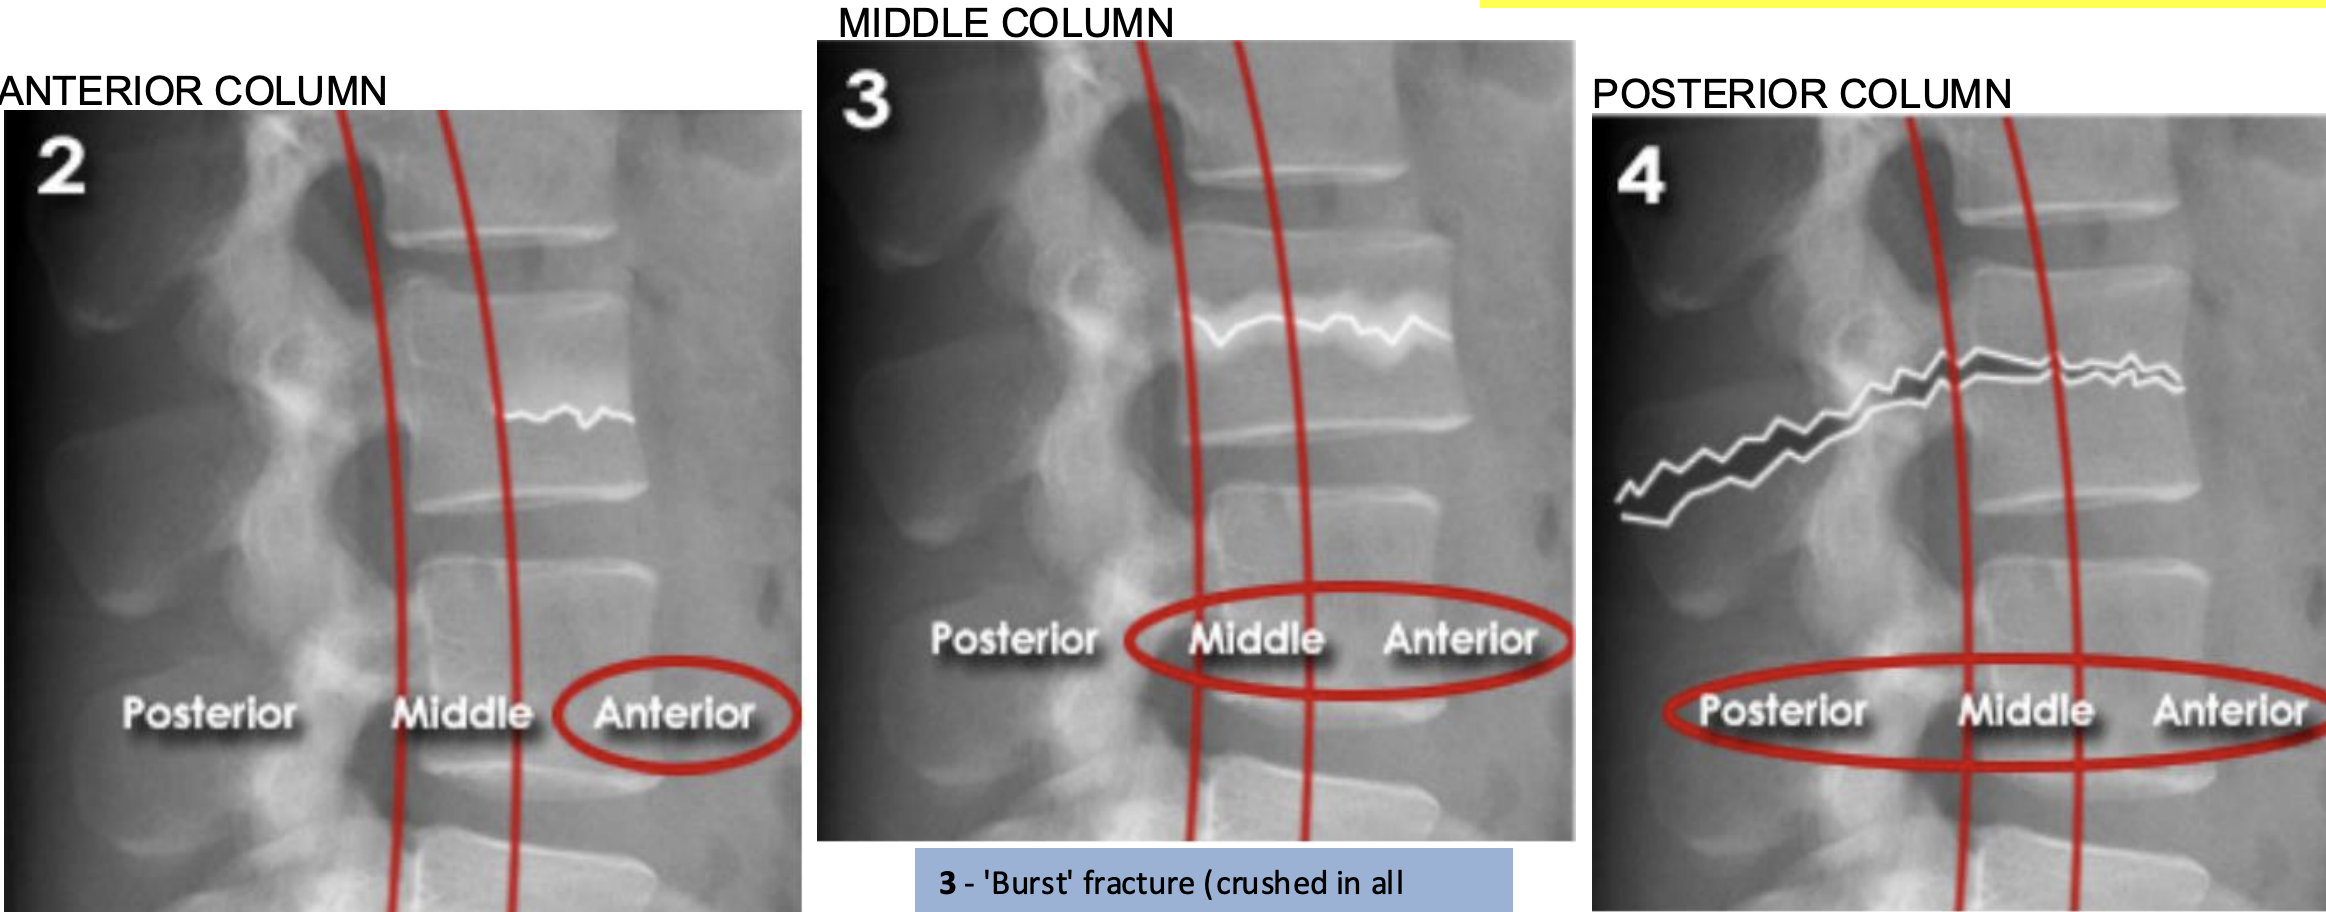

Lumbar three column model

Divides the spine into three columns: anterior, middle, and posterior

Used to determine the stability of thoraco-lumbar spine fractures

severity depends on how many columns are implicated

If spinal instability is suspected further imaging with CT or MRI should be considered

ANTERIOR (Stable):

Anterior compression injury

e.g. compression fractures (most common)

between the anterior longitudinal ligament to the middle of the vertebral body

MIDDLE (unstable):

'Burst' fracture (vertebral body crushed in all directions) due to axial loading

between middle of vertebral body to posterior longitudinal ligament

POSTERIOR (unstable):

Flexion-distraction fracture (caused by severe compression or rotation)

between posterior longitudinal ligament to spinous process

spinal cord implicated